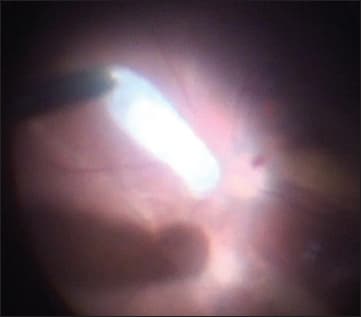

The first step in removing the larva was that it was fixed by the aspiration cannula and tucked up for expansion to a 2-mm sclerotomy (Figure 2). Next, we carefully removed the larva from the vitreous cavity with vitreal forceps, without damaging its integrity (Figure 3), and we placed it in physiological solution for further identification. As the final step, we performed endolaser coagulation around the retinal break and closure of the sclerotomy.

Figure 2. The larva was fixed by aspiration cannula.